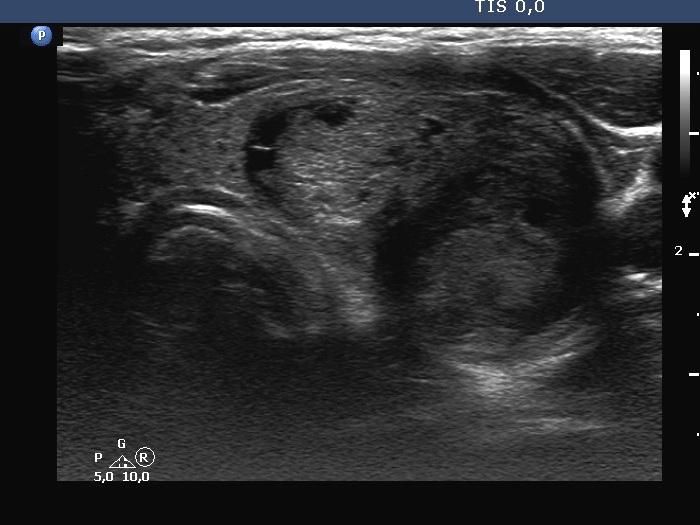

Ultrasonography. The thyroid was minimally-moderately hypoechogenic. There was a large solid-cystic nodule in the left lobe. The nodule belonged to multi-chambered, central subgroup. The nodule did not increase in size in the last ten years.

Comment. The proportion of cystic areas is less than 50%, therefore this nodule should be held as a solid one which has cystic areas.